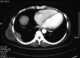

Chest mass

A chest radiograph, called a chest X-ray (CXR), or chest film, is a projection radiograph of the chest used to diagnose conditions affecting the chest, its contents, and nearby structures. Chest radiographs are the most common film taken in medicine. [Source: Wikipedia ]